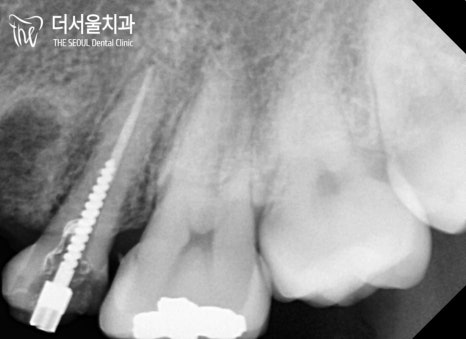

우선 잔존조직이 남아있지 않도록

깨끗하게 발치를 하였으며,

살릴 수 있는 곳들은 근관치료를 했습니다.

어느 정도 썩어있는 치아들이 모두 개선될 때쯤!

더서울에서는 아래와 같은 계획을 세웠습니다.

장치를 부착하여 견인을 하고 있는 모습입니다.

이후 치열 정돈 및 교합, 컨택 등을 맞춰가며

클린체크에서 확인했던 모습처럼

개선을 도와드릴 예정입니다 🙂